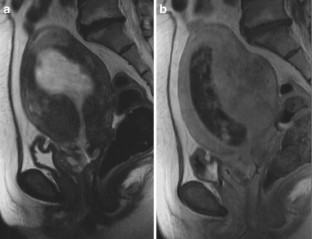

The endometrial cavity may demonstrate various imaging manifestations such as normal, reactive, inflammatory, and benign and malignant neoplasms. We evaluated usual and unusual magnetic resonance imaging (MRI) findings of the uterine endometrial cavity, and described the diagnostic clues to differential diagnoses. Surgically proven pathologies of the uterine endometrial cavity were evaluated retrospectively with pathologic correlation. The pathologies included benign endometrial neoplasms such as endometrial hyperplasia and polyp, malignant endometrial neoplasms such as endometrial carcinoma and carcinosarcoma, endometrial–myometrial neoplasm such as endometrial stromal sarcoma, pregnancy-related lesions in the endometrial cavity such as gestational trophoblastic diseases (hydatidiform mole, invasive mole and choriocarcinoma) and placental polyp, myometrial lesions simulating endometrial lesions such as submucosal leiomyoma and some adenomyosis, endometrial neoplasms simulating myometrial lesions such as adenomyomatous polyp and endometrial lesions arising in the hemicavity of a septate/bicornate uterus, and fluid collections in the uterine cavity (hydro/hemato/pyometra). It is important to recognize various imaging findings in these diseases, in order to make a correct preoperative diagnosis.